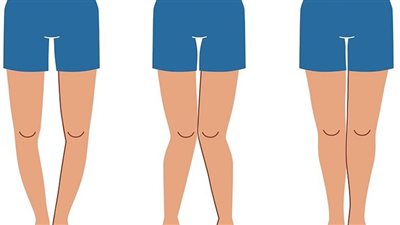

كشف الدكتور أحمد عبد الفتاح، استشاري جراحة العظام والعمود الفقري جامعة الفيوم، والتي عادةً ما تكون بعد سن الـ 3 سنوات، حيث يظهر ساق الطفل بها أعوجاج أما للداخل أو الخارج، وعادة ما يتم علاج تقوس الساقين بشكل تلقائي دون تدخل طبيب حتى عمر الـ 3 سنوات، ولكن في حالة استمرار تقوس الساقين، فإن هذا الطفل من الممكن أن يكون مصاب بمرض "بلاونت"، أي عدم نمو الساق بشكل طبيعي.

وأشار إلى أن عملية تقوس الساقين، للحالات التي تعاني من مرض "بلاونت" تنقسم إلى نوعين، فهناك حالات تحتاج إلى عملية جراحية وتكون عبارة عن عملية تعديل مراكز النمو، والآخرى عملية قطع عظم قصبة الساق.